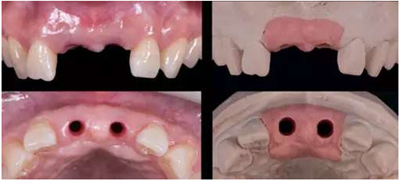

蠟型制作完成后,翻制硅橡膠導(dǎo)板,根據(jù)穿齦輪廓來修整人工牙齦,保證修整后鄰緣的位置與診斷蠟型一致。即根據(jù)硅橡膠導(dǎo)板及齦緣修整牙齦范圍,隨后進(jìn)行穿齦輪廓的修整。

修復(fù)種植臨時(shí)基臺(tái)

本病例選用光固化樹脂材料制作過渡義齒,光固化樹脂材料豐富,方便操作,戴牙出現(xiàn)問題時(shí),也方便及時(shí)進(jìn)行修復(fù)。

種植過渡義齒完成(螺絲固位)

種植過渡義齒試戴,調(diào)整唇側(cè)凸度,切端位置

患者剛戴入過渡義齒時(shí),發(fā)現(xiàn)牙齦泛白,范圍不超過鄰牙終點(diǎn)。若患者休息10分鐘后,牙齦顏色恢復(fù)正常,則說明穿齦輪廓設(shè)計(jì)合理。